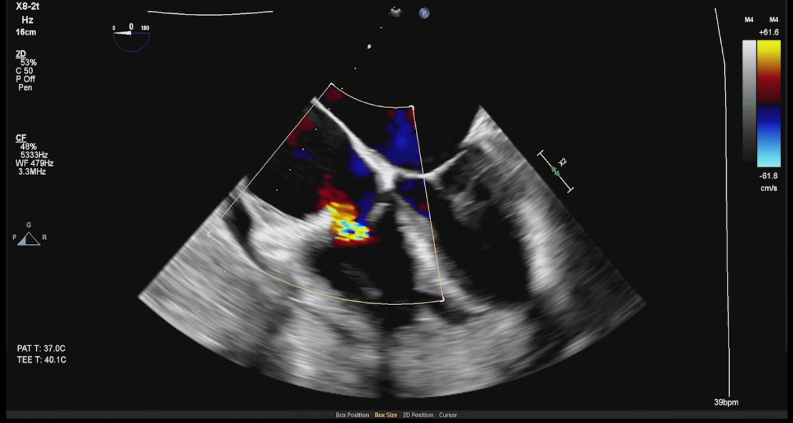

全麻下经右颈静脉入路,在食道超声及放射线引导下,将三尖瓣导丝输送导管经三尖瓣指引导管送至右心室,定位三尖瓣瓣环穿刺位点。穿越导丝连接高频发生器穿刺三尖瓣环(图2),在三尖瓣瓣环上植入一对锚片。通过缩短两个锚片之间的距离折叠三尖瓣瓣环,并通过3D-TEE、2D-TEE确认瓣环折叠及三尖瓣反流情况,最终实现三尖瓣瓣环的二瓣叶化(视频1),从而降低因瓣环扩大、瓣叶关闭不全产生的三尖瓣反流。

图2 :穿越导丝穿刺三尖瓣环(a:2D-TEE,b:3D-TEE)